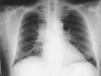

Varón de 64 años fumador con tos y expectoración hemoptoica de 2 meses de evolución